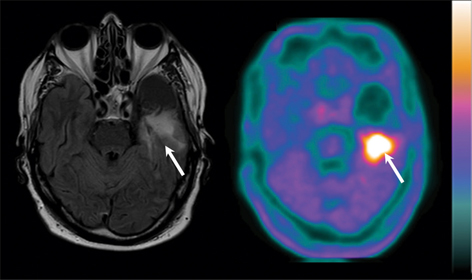

18F-FDG is useful for differentiating high-grade gliomas from other types of brain tumors (18). In the specific setting of glioblastomas, 18F-FDG is particularly sensitive at the initial stage of the diagnosis (19, 20), an example of which is given in Figure 1. In a study involving 31 newly diagnosed glioblastomas, Colavolpe et al. found an uptake of 18F-FDG in these tumors with a tumor-to-background ratio max (TBRmax) of 1.4±0.8 (12). However, differential diagnosis at the initial stage with 18F-FDG may be difficult to achieve due to the low specificity of this radiotracer. Indeed, brain lymphomas can display a higher glucose metabolism uptake than high-grade gliomas (21). Moreover, nonneoplastic neurological diseases can mimic brain neoplasms on 18F-FDG, including pyogenic abscesses, tuberculosis, fungal infections, or sarcoidosis (22). Studies comparing the 18F-FDG and amino acid tracer uptake in the assessment of brain tumors demonstrated significantly higher tumor to brain contrast with amino acid PET than with 18F-FDG (2325), demonstrating a higher sensitivity of amino acid tracers for glioblastoma detection.

Fig 1

Figure 1 Primary diagnosis of a right frontal glioblastoma in a 79-year-old man following acquisition of axial slices of T1-weighted gadolinium-enhanced MRI (left side) and 18F-FDG PET (right side). The right frontal glioblastoma is contrast-enhanced on MRI (white arrow) and shows an extensive uptake of 18F-FDG PET (white arrow), despite the high uptake in surrounding normal brain tissue.